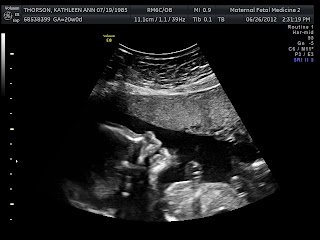

So here he is--Baby Boy Thorson. They paid a lot of attention to his heart, then looked at his stomach, kidneys, bladder, spine--all sorts of stuff. Everything looks great. 10 fingers, 10 toes, and 1 little something else (not pictured). My favorite picture is of his little lips and nose! We also watched him gulping down amniotic fluid. Technology is amazing. And you know, the formation of human life is pretty cool too. And in the waiting room, Mom became the first to feel him kick from the outside!

We're so excited to have our little Superman.